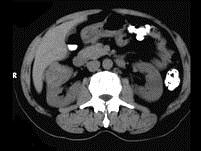

问题 男,56岁,无痛性全程血尿1个月,CT平扫及增强检查如图,下列说法正确的是 ( )

选项 A、右肾静脉及下腔静脉内未见充盈缺损影 B、考虑为右肾上极的肾癌 C、增强扫描皮质期,病灶强化明显,但仍低于肾皮质的强化 D、增强扫描实质期,该灶强化迅速减退,可清楚的分辨其轮廓 E、在右肾上极,肾脏局部隆起,平扫时其密度与肾相近,不易分辨其轮廓